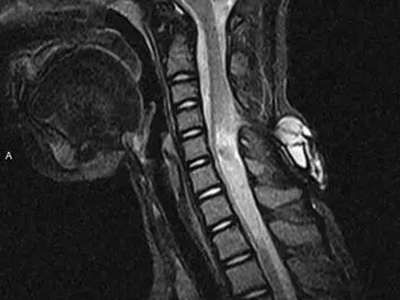

隐性脊柱裂颈部CT有脊髓变形多出一块图

隐性脊柱裂患者的颈部拍摄CT,可观察到颈椎后方有一片较透亮、近似圆锥形、向下低垂的多余区域,属于脊髓脊膜膨出的表现,一般由脊髓空洞囊肿、脊髓低位导致。